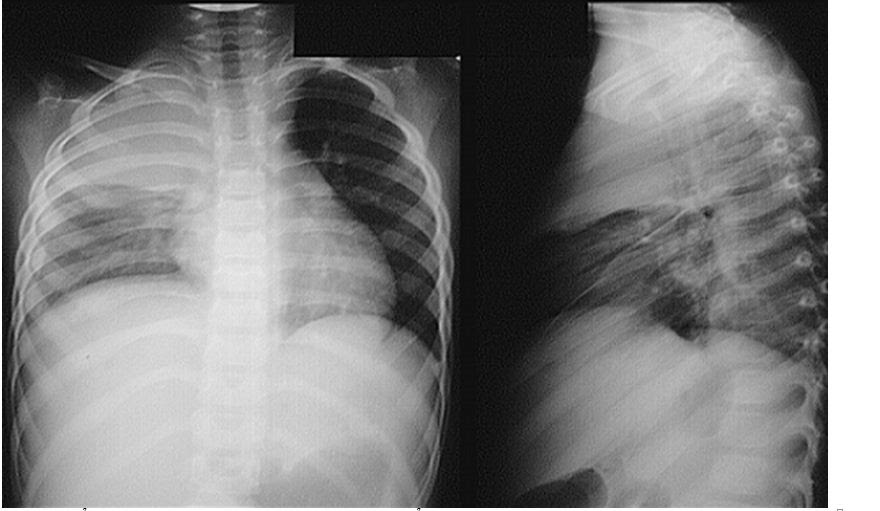

Chụp X-quang.

Click vào ảnh để xem 4 hình ảnh minh họa